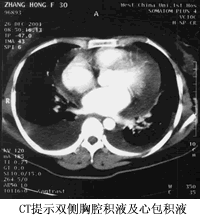

双侧胸腔积液、心包积液

胸腹部CT:肺纹理增粗模糊,右侧液气胸,左侧少量胸腔积液;心包积液。肝内多发钙化灶,脾稍大。(见图1)